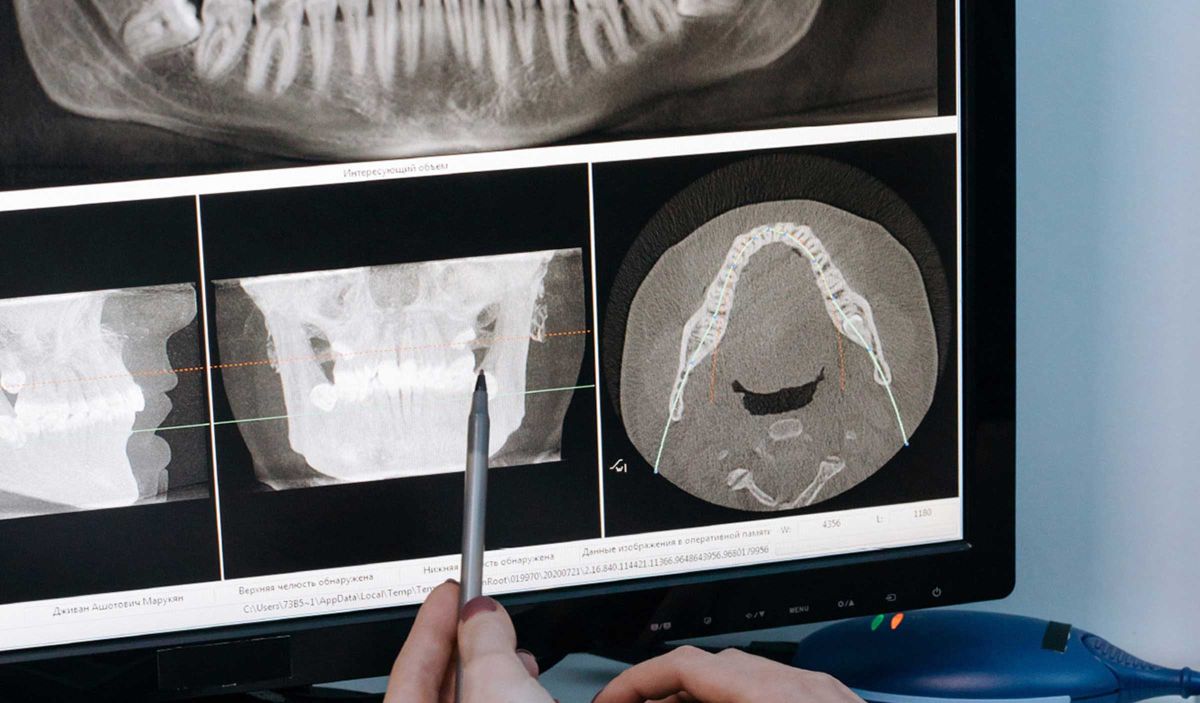

Warum Röntgen? Röntgenbilder verschaffen uns einen ersten generellen Überblick über Ihre Zähne, deren Stellung, Wurzeln, eventuelle Zysten, etc. Regelmäßige, digitale Röntgenuntersuchungen machen eine rechtzeitige Behandlung eventueller Erkrankungen möglich, denn auf unseren digitalen Aufnahmen bleibt nahezu nichts verborgen.

Karies zwischen zwei Zähnen oder unter vorhandenen Füllungen, chronische Entzündungen, verlagerte Weisheitszähne, alles Dinge, welche normal nicht sichtbar wären, deckt das digitale Röntgenbild auf. Weiterführend besteht noch die ganzheitliche Diagnose, so sind Sie sicher, daß nichts verborgen und unbehandelt bleibt.